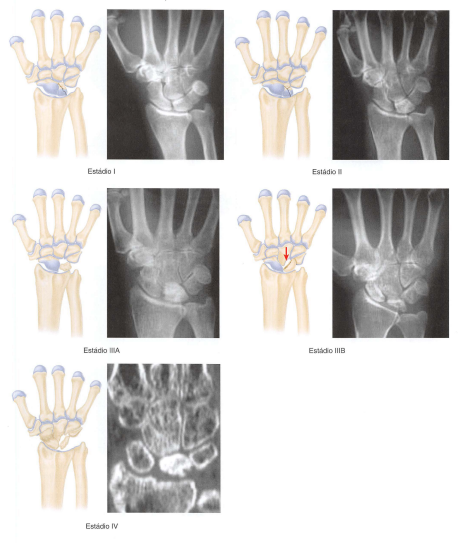

11

Q

Doença de Kienbock

• Estadiamento (classificação) de Licthman (4):

Radiográfico

A

• Grau 1 - RX normal // RNM → isquemia, necrose, revascularização

• Grau 2 - RX com esclerose do semilunar

• Grau 3 - Colapso do semilunar

• 3Asem instabilidade (ângulos carpais mantidos)

• 3Bcom instabilidade (ângulos carpais não mantidos)

• Grau 4 - Artrose cárpica